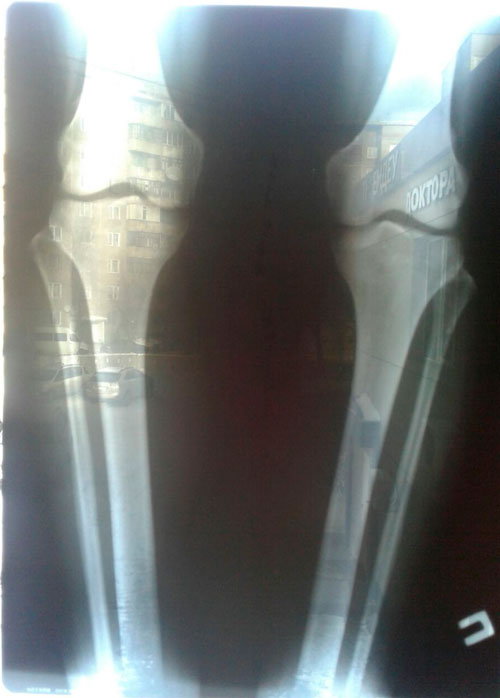

РЕНТГЕН ДО ОПЕРАЦИИ